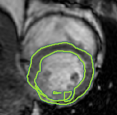

4.2 Visual assessment

We select the case that achieves the highest and lowest dice score for visual assessment. Fig. 4 shows example segmentation results where the proposed method achieved the highest agreement with the ground truth delineations. Fig. 5 shows example segmentation results where the proposed method achieved the lowest agreement with the ground truth delineations.